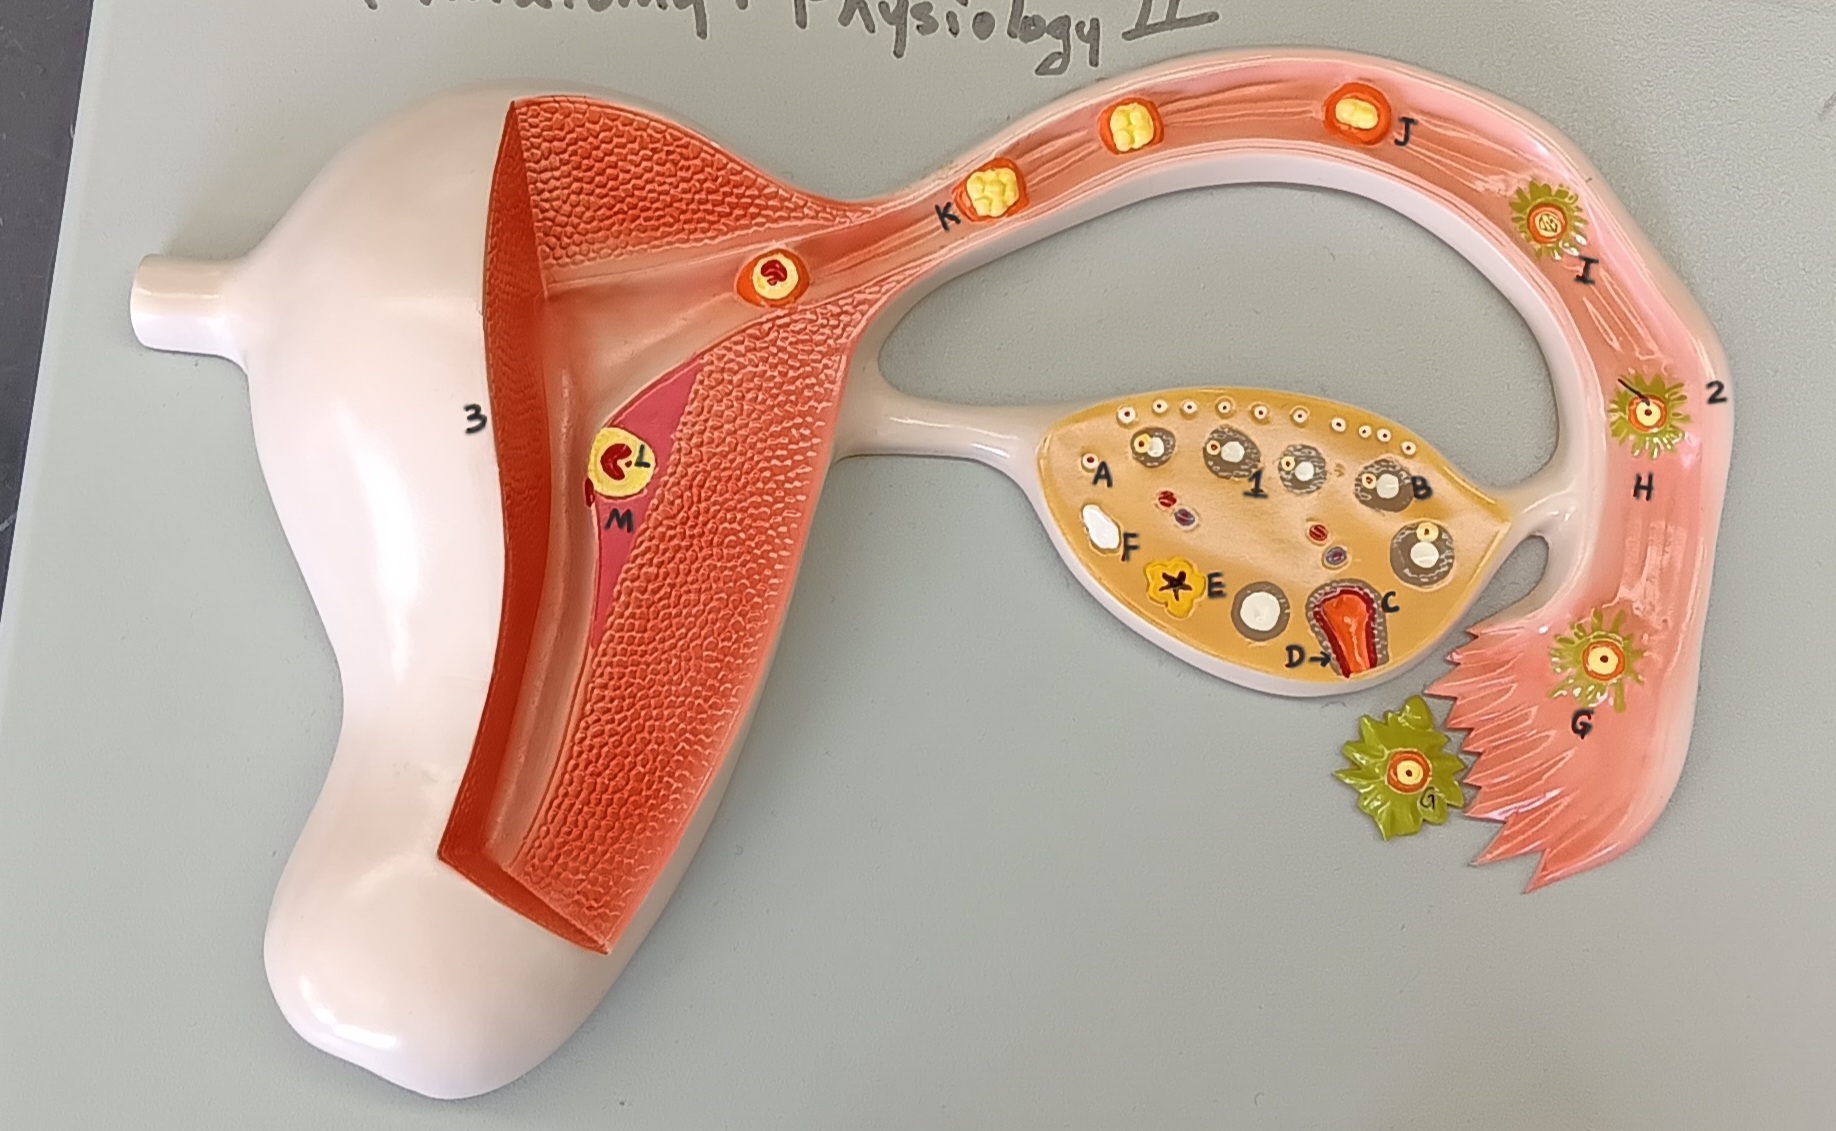

ovary

1

primordial follicle

a

secondary follicle

b

ruptured follicle

c

granulosa cells

d

corpus luteum

e

secondary oocyte

g

ovum

h

zygote

i

blastocyst

l

endometrium

m

corpus albicans

f

uterus

3

fallopian tube

2